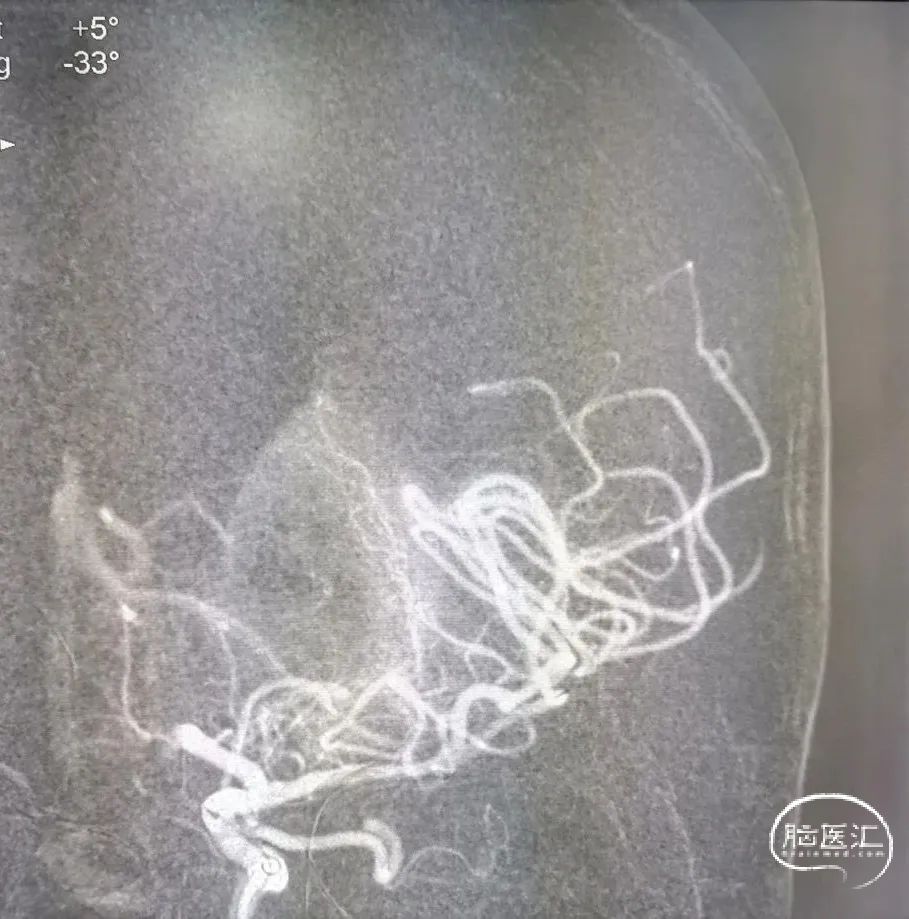

再次超选并将Syphonet®取栓支架释放后造影见血流通畅,回收取栓支架后血管再次闭塞,遂将4.5*28mm 支架置于大脑前动脉释放,支架释放后造影血流恢复满意。

通过中间导管将保护伞到位,退出中间导管,长鞘退至颈总动脉,4.5*30mm 球囊扩张颈内动脉狭窄段,球扩后满意,释放7*40mm 支架。

术后正侧位造影:全程血流恢复满意。